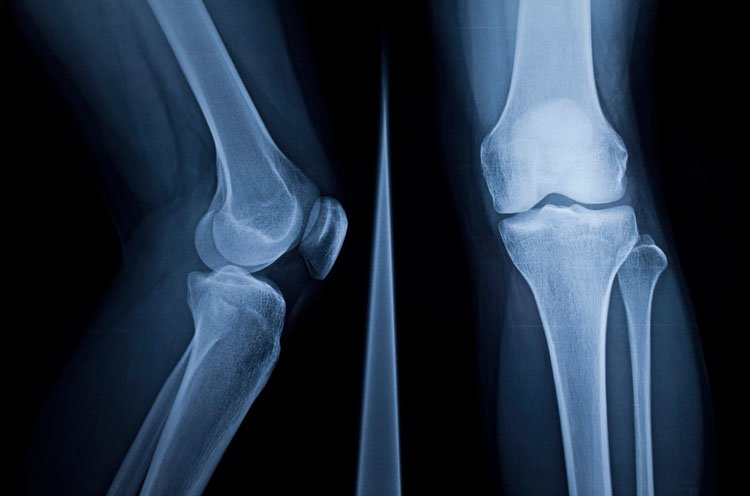

leg x ray